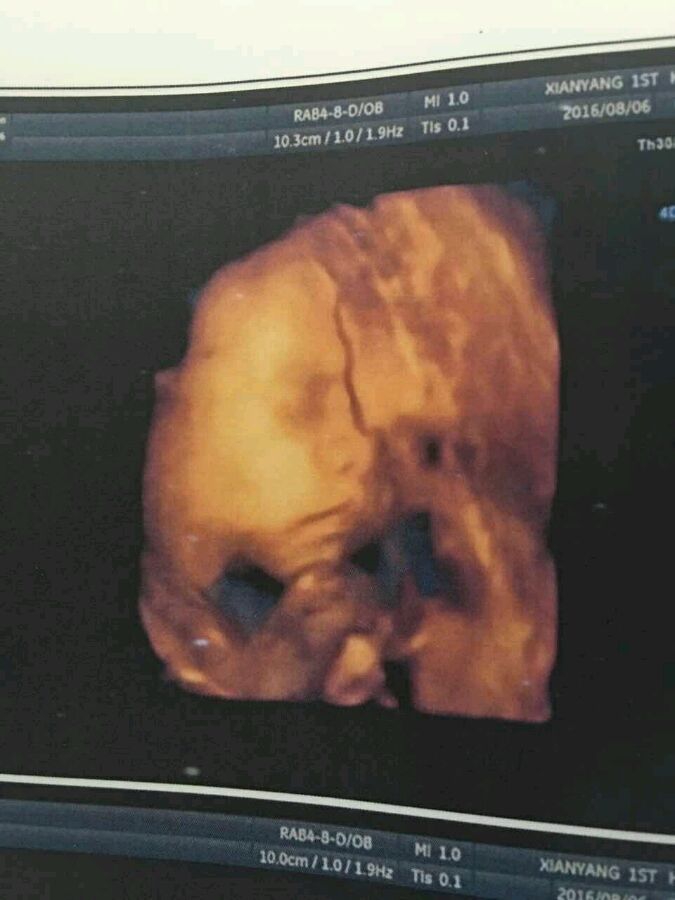

#一楼献给国家#看图片这个血管怎么了。